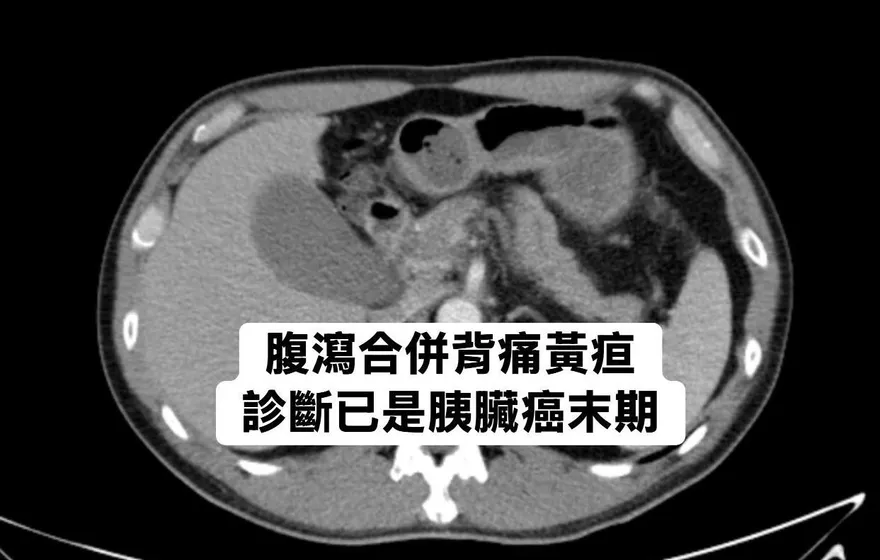

胰臟癌

林相宏醫師

肝膽腸胃科

胰臟癌檢查